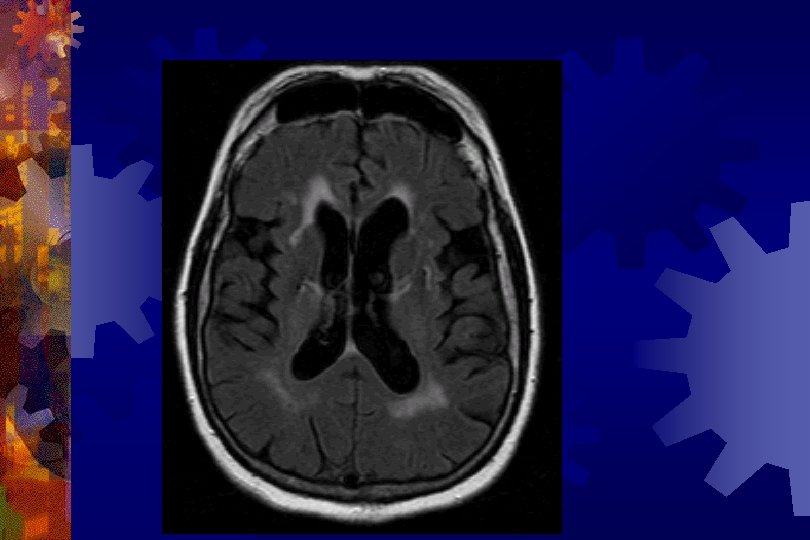

Vascular dementia ® Stepwise progression ® Focal neurological deficits ® Retrieval memory deficit ® Psychomotor slowing, apathy ® Neuroimaging ® Vasculitis/hypercoagulable/stroke workup

Normal Pressure Hydrocephalus ® Dementia ® Urinary Incontinence ® Gait Apraxia ® Workup ® CT or MRI ® LP ® Cisternogram ® Treatment